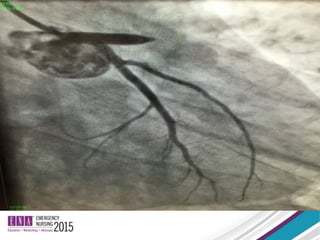

To Cath Lab with CPR

• Witnessed VF especially with chest pain

• Bystander CPR

• Young without comorbidities

• Excellent CPR

• Short arrest to treatment

• ED arrest with STEMI/STEMI equivalent

To Cath Lab after ROSC

• Conventional STEMI or STEMI equivalent

criteria

• Ischemic EKG that PERSISTS 20-30 minutes

into resuscitation

• Electrical Storm/Persistent Ventricular

Arrhythmia

Hollenbeck et al 2014

Resuscitation

• Early cardiac catheterization is associated

with improved survival in comatose

survivors of cardiac arrest without STEMI